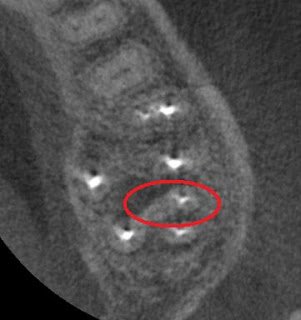

The patient understandably harbored a very negative opinion of the success rate of root canal therapy. When patients harbor this attitude, treatment planning long, challenging retreatments with less than perfect success rates is usually out of the question. I recommended extraction of tooth #15, especially since saving the tooth would also require the investment of a new crown. I offered the alternative of a CBCT evaluation to aid in treatment planning any approach to saving the tooth. The patient understood my concerns, and opted for the CBCT. Here are some selected images from the CBCT.

Circled is the MB root in cross section. From this view, it becomes apparent there is untreated canal anatomy in the form of a MB2 canal.